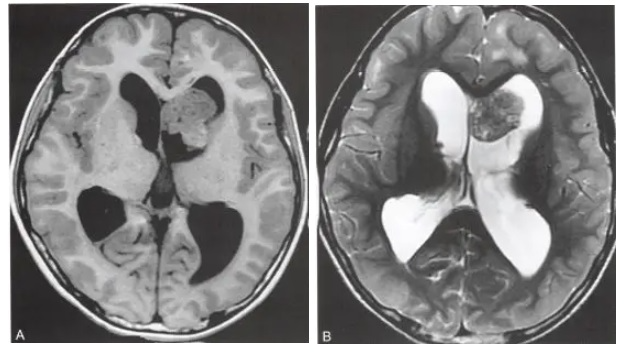

间变形星形细胞瘤属于WHO III 级。这种高级别的肿瘤特点是弥漫浸润生长,且该星形细胞肿瘤占脑胶质瘤的四分之一,预后较差。好发年龄为40-50岁。手术是间变性星形细胞瘤的首选治疗方法,目的是尽可能多地切除肿瘤组织,以减轻症状并延长生存期。由于肿瘤通常位于大脑深处或附近重要功能区,完全切除可能较困难。手术后常需进行放射治疗。

一般增强后扫描多为不规则环状强化,少数为结节状、斑片状强化。